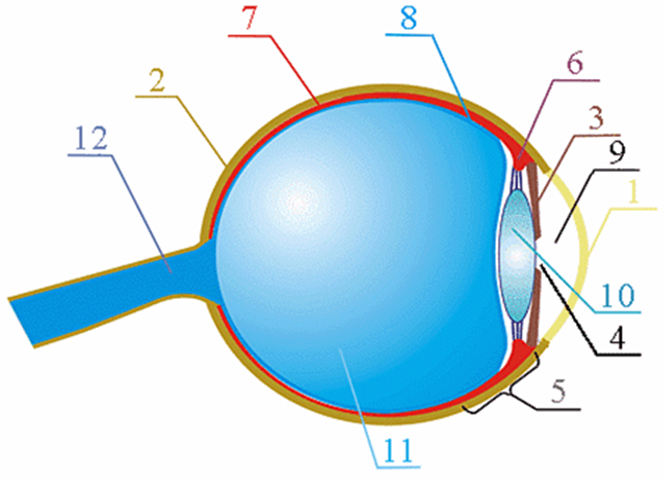

КТ-графики и изображение строения глаза